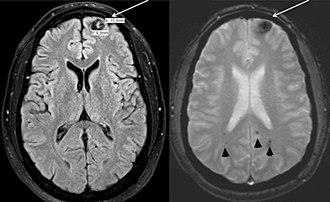

Самый большой кавернозный порок развития человека показан в левом лобном полюсе. Это поражение имеет классические признаки кровотечения (белые стрелки). Могут наблюдаться и другие поражения, совместимые с кавернозными пороками в других областях мозга (стрелки). Синдром Польши. [2]